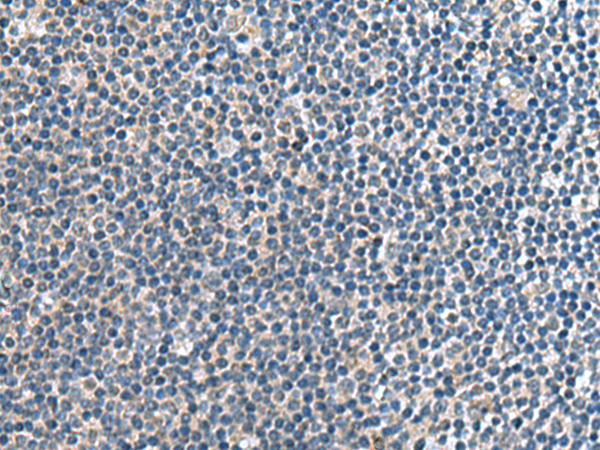

分类: 科研抗体货号: P10237别名: TIH1应用: IHC反应种属: Human, Mouse, Rat